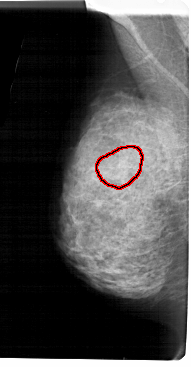

A_1939_1.LEFT_CC

LEFT_CC LINES 5341 PIXELS_PER_LINE 2416 BITS_PER_PIXEL 12 RESOLUTION 43.5 OVERLAY

FILE: A_1939_1.LEFT_CC.OVERLAY

TOTAL_ABNORMALITIES 1

ABNORMALITY 1

LESION_TYPE CALCIFICATION TYPE AMORPHOUS DISTRIBUTION SEGMENTAL

ASSESSMENT 4

SUBTLETY 3

PATHOLOGY BENIGN

TOTAL_OUTLINES 1

BOUNDARY